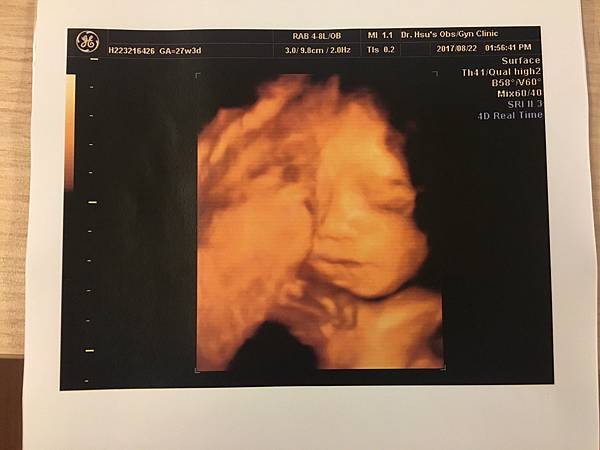

27週 自費4D立體超音波

這個基本上就是娛樂性質大於產檢性質啦

超期待可以看到4D的皮妞

照之前有好好跟她說,她也超乖乖配合

剛開拍1分鐘就微笑了

(雖然拍到後面他就不想配合了覺得有完沒完吧)

天啊,我的寶貝在對我們微笑![]()

這看起來應該比較像媽媽吧哈哈

生命真的好奧妙,妳從一個小米粒長到現在這麼大了